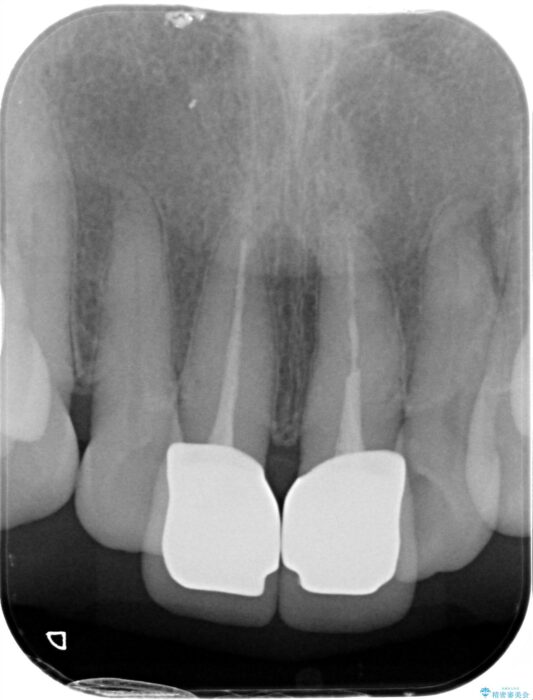

前歯の差し歯(クラウン)が黒ずんでいるとご相談にいらっしゃった患者様です。

根管治療は行わず、クラウンのやり替えのみ行います。

審美性に優れるジルコニアクラウンによる治療を計画します。